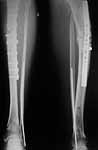

Hello Bill,

BB> Bob Winquist gives a good OTA Basic Fx course talk on how to avoid valgus nailing of proximal tibial fractures with much emphasis on starting point -

THX for the good source. We use an "alternative" technique - a small wire distractor which allows to avoid this problem rather easily (image attached). And i guess it could help in the case but the patient is far from here.